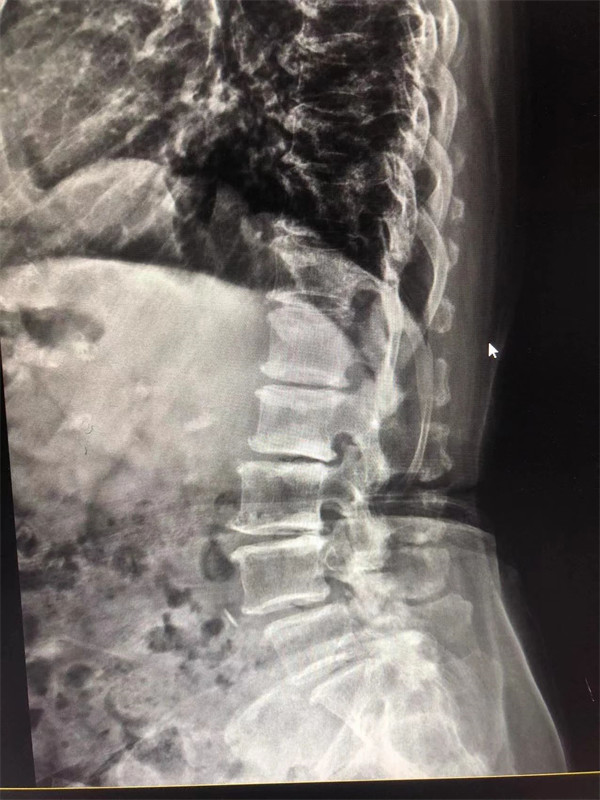

戈主任仔細詢問阿婆病情癥狀,綜合查體及MRI片情況,認為阿婆有明顯的腰椎滑脫,腰椎管狹窄,這是引發(fā)阿婆病痛的主要因素。

手術(shù)前↓